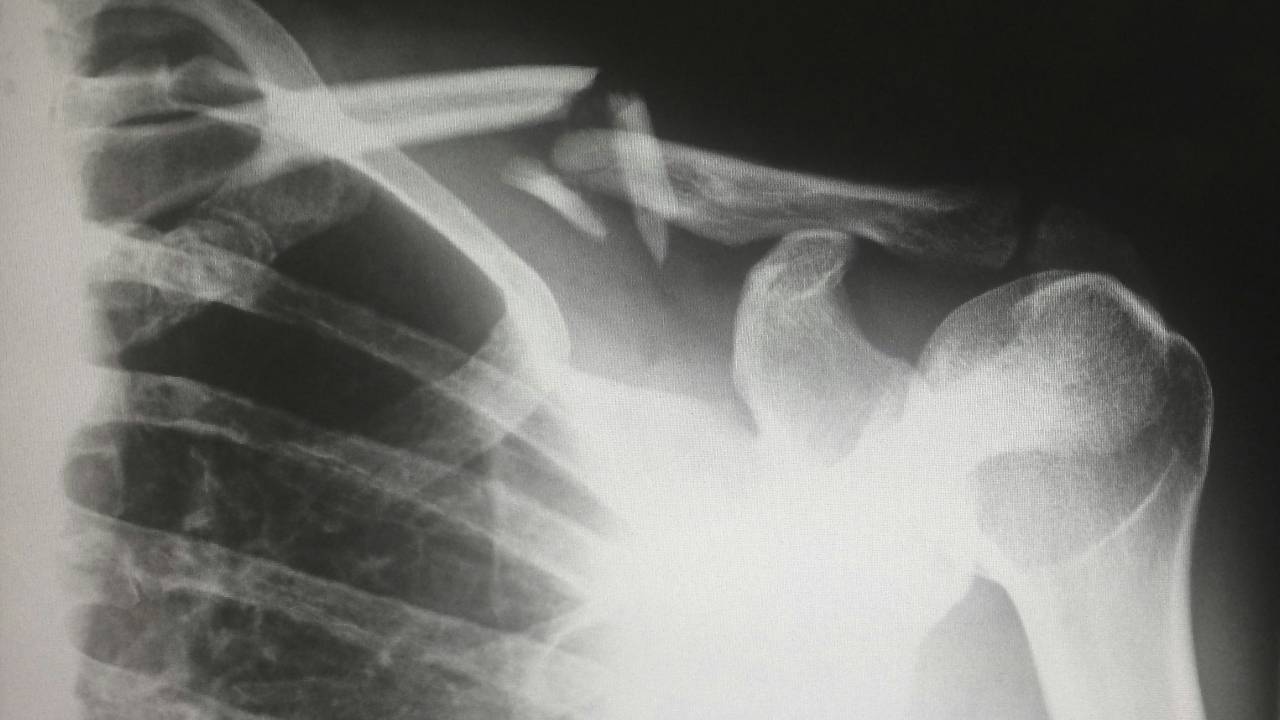

There’s also a difference between an injury that happens suddenly...a clear break with a clear timeline for recovery and the gruelling drag of chronic, overuse injuries. The latter can eat away at motivation, making young athletes question their love for the sport as aches linger and improvement stalls. Sometimes the bravest choice is rest but a hard admission in a culture that glorifies toughness.

I’ve seen the difference a mindset shift can make. When Isaac broke his wrist, he was nervous to play again. We worked on visualisation...imagining himself tackling confidently, feeling every movement in his mind before returning to the pitch. When he finally did, he matched those imagined feats on the field, returning with not just healed bones, but a stronger spirit. Tom’s knee injury looked like it would drag him down, but by reframing it as an opportunity...focusing on schoolwork and developing other parts of his game, he emerged happier and more balanced. The setbacks became a springboard for growth.